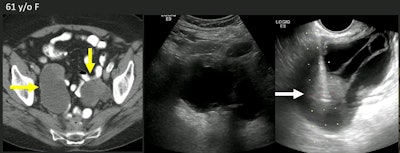

Researchers at the ARRS annual meeting presented the results of a 20-year study showing the efficacy of biopsying pelvic lesions with transvaginal ultrasound (TVUS). Here, images show bilateral cystic masses in a 61-year-old woman with a history of metastatic colon cancer. The middle image is a transabdominal ultrasound image that shows the cystic aspect, but not the solid parts. The right image is a TVUS image showing a solid nodule. Diagnostic concordant biopsy showed this was a metastatic colonic adenocarcinoma. Images courtesy of ARRS.The researchers found that a TVUS-guided approach significantly decreased the distance to the biopsy target by an average of 10.7 mm; transabdominal ultrasound had an average distance to biopsy target of 86 mm (p < 0.0001).

Also, the average lesion size on TVUS was 40 mm. Targets at or above the vaginal cuff and up to above the acetabular roof were also accessible.